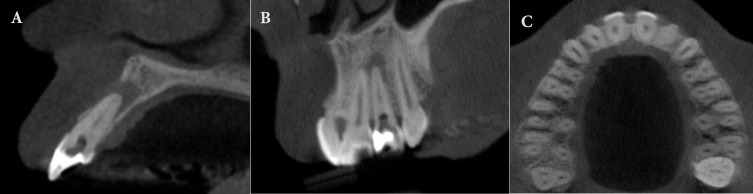

Endodontic management of teeth afflicted with pulp canal obliteration faces a challenge due to the heightened risk of complications including excessive wear, perforation, and suboptimal chemomechanical preparation. This report aims to elucidate the clinical endodontic strategy employed in addressing pulp canal obliteration after a history of dental trauma and an associated periradicular lesion in an upper lateral incisor. A patient visited the dental emergency department with symptoms of apical swelling, acute persistent pain, and discoloration of tooth 22. Following comprehensive clinical evaluation and cone-beam computed tomography, the diagnosis of pulp canal obliteration involving the cervical and middle thirds of the tooth, alongside an acute periradicular abscess was established. Root canal was accessed using tomographic image planning, augmented by loupe magnification and ultrasonic instrumentation. Precise identification of the access cavity was radiographically confirmed, preceded by thorough irrigation with 2.5% sodium hypochlorite and subsequent cervical and middle third preparation. Verification of the working length by an electronic apex locator ensured precise apical preparation, followed by passive ultrasonic irrigation to optimize disinfection and to enhance penetrability of intracanal calcium hydroxide medication, administered for 15 days to eliminate microbial invasion. Upon resolution of symptoms, root canal obturation employing thermo-mechanical compaction and coronal sealing with composite resin was accomplished. Radiographic assessment after a one-year interval presented evidence of lesion regression and bone repair. Subsequent cone-beam computed tomography imaging at the three-year follow-up confirmed complete healing of the periradicular tissues, attesting to the efficacy of the endodontic intervention.